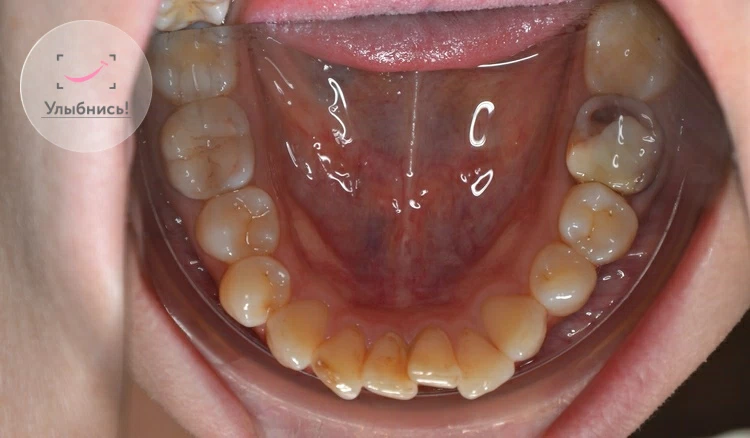

Процедура профессиональной гигиены полости рта у подростков проводится опытным стоматологом-гигиенистом и включает несколько этапов. Сначала врач проводит осмотр полости рта, оценивает состояние зубов и десен. Затем проводится профессиональная чистка зубов с использованием ультразвукового аппарата или специальных инструментов для удаления зубного камня и налета. После этого поверхность зубов полируется специальными пастами для удаления пигментации и улучшения гладкости эмали. В конце процедуры наносится фторсодержащий гель или лак для укрепления эмали и предотвращения кариеса. Вся процедура обычно занимает от 30 до 60 минут и проходит безболезненно.

Этапы профессиональной гигиены⁚

- Осмотр полости рта

- Удаление зубного камня и налета

- Полировка зубов

- Нанесение фторсодержащего геля или лака